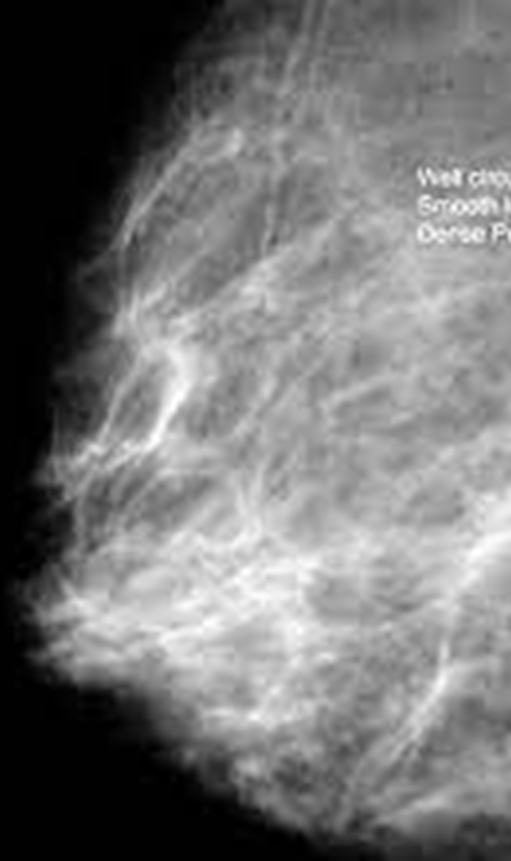

What is this image showing?

fibroadenoma on mammo